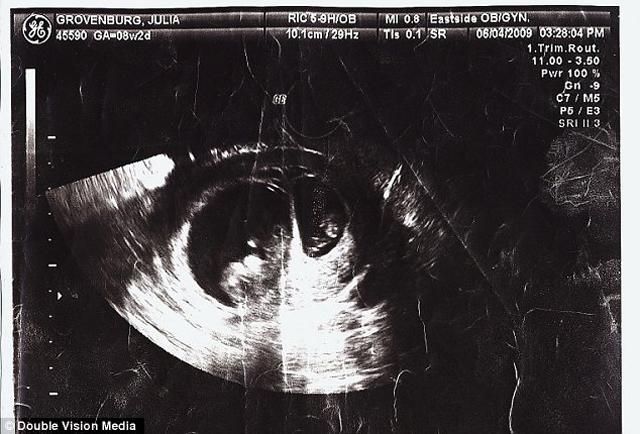

03/06/2018 15:17Có thai nhưng vẫn… dính bầu, người mẹ sinh 2 đứa con chỉ trong vòng 2 tuần

Từng bị vô sinh trong gần 3 năm, gia đình cô Julia Grovenburg và chồng cô, anh Todd, đã vô cùng buồn bã, tuyệt vọng. Tuy nhiên, may mắn đã mỉm cười với hai vợ chồng vào cuối năm 2009 khi cô Grovenburg có kết quả dương tính với que thử thai.

Trong lần siêu âm đầu tiên, các bác sĩ xác định trong bụng Julia có một bé gái đang phát triển. Nhưng ngay sau đó, họ lại phát hiện một bào thai nhỏ hơn hẳn đang nằm bên cạnh. Tuy nhiên, xét về kích thước, một bé nhỏ hơn hẳn và không thể có cùng số tuần với bé còn lại. Từ đó, trường hợp đây là cặp song sinh bị loại bỏ. Các bác sĩ đã không thể giải thích được điều gì đang xảy ra trong cơ thể cô Julia.

Ở tuổi 33, cô Julia đã khiến các bác sĩ và chuyên gia sinh sản phải kinh ngạc vì có tới 2 bào thai hoàn toàn không phải là sinh đôi trong bụng. Các bé được thụ thai ở thời điểm khác nhau, cách nhau khoảng 2 tuần rưỡi và cả ngày dự sinh cũng khác nhau.

Bác sĩ phu trách chính của cô Julia cho biết: “Đây là trường hợp bất thường, nhưng không thể không xảy ra. Chúng tôi từng khi nhận vài trường hợp mẹ có hai tử cung nên thụ được 2 bào thai ở thời điểm khác nhau. Tuy nhiên, với cô Julia là khó lý giải nhất”.

Trường hợp của cô Julia, khi thụ thêm thai trong quá trình mang bầu, được gọi là Bội thụ tinh khác kỳ. Tuy rất may mắn khi có tới hai em bé, nhưng lại rất nguy hiểm tới sức khỏe cũng như tính mạng của chính người mẹ và các con. Bé thứ hai có thể bị sinh non, suy phổi hoặc suy dinh dưỡng.

Dù vậy, khoảng cách 2 tuần tuổi của các bé nhà Julia có thể sẽ không quá nguy hiểm. Cô Julia đã được các bác sĩ đặc biệt lên kế hoạch và chế độ dinh dưỡng để đảm bảo dưỡng chất cho cả hai bé được khỏe mạnh như nhau. Julia cũng đã theo lời khuyên của bác sĩ, lựa chọn phương pháp mổ để đón hai bé chào đời thật khỏe mạnh.